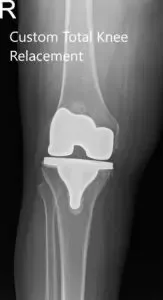

Postoperative X-ray of the right knee showing AP and Oblique views.

He had an excellent recovery from their total knee replacement in the postoperative period. He was able to walk with support the same day of the surgery. The pain was managed with oral medications and was started on aspirin for DVT prophylaxis. On his subsequent visit, the staples were removed and the range of motion was found to be full. He was stressed on the importance of strict control of blood sugar levels and compliance with physical therapy.

Subsequently, the patient followed three months later stating complete relief of pain in the right knee and decreased pain on the left side. He was planning to travel to Phoenix on his grandson’s graduation and was happy with the prospect of doing it without pain. He regularly follows up and will plan for the left knee replacement in the future if required.